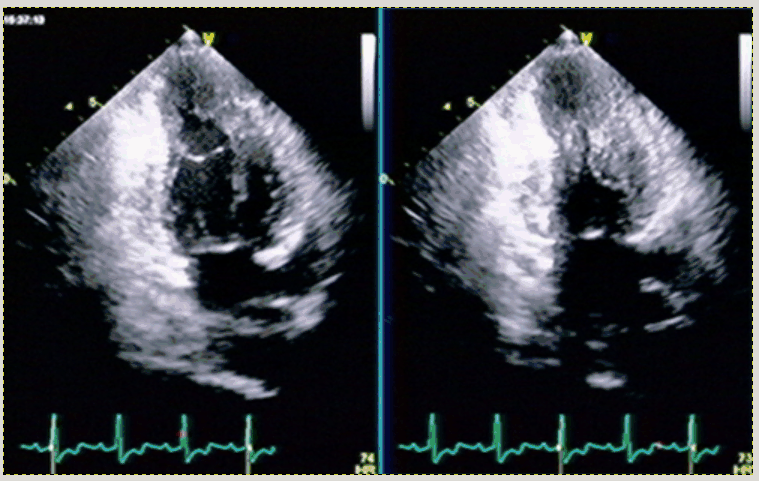

15-28 Posterior Wall AMI

15-29 ¸Å¤¤IWMI¤ÈPWMI¤ÈLWMI¡¤¿´¼¼¿´ÇPosterior Wall AMI

15-28 µÞÀ¤ÇV1¡ÁV4¤Þ¤Ç¤Î¹â¤¤RÇÈ¡¤STÄã²¼¤È¾å¸þ¤TÇÈ¡¥

²¼Êɹ¼ºÉ¤Ï¤Ê¤¯¡¤ÆÈΩ¤·¤¿¸åÊɹ¼ºÉ¡¥¶»ÉôRÇȤÏV2¤¬ºÇ¤â¹â¤¯V6¤¬ºÇ¤âÄ㤤¡¥

ECG 15-28

15-29 II,III,aVF¤ÎQÇȤÈV1V2¤ÎRÇȾ徺¡¥¸Å¤¤²¼ÊɸåÊɹ¼ºÉ¡¥

ECG 15-29